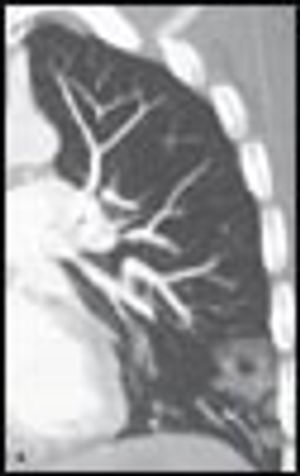

A51-year-old man who was an active injection drug user was admitted to the ICU with septic shock and severe respiratory distress. Notable findings were fever, multiple opacities on a chest radiograph, and an elevated white blood cell count.